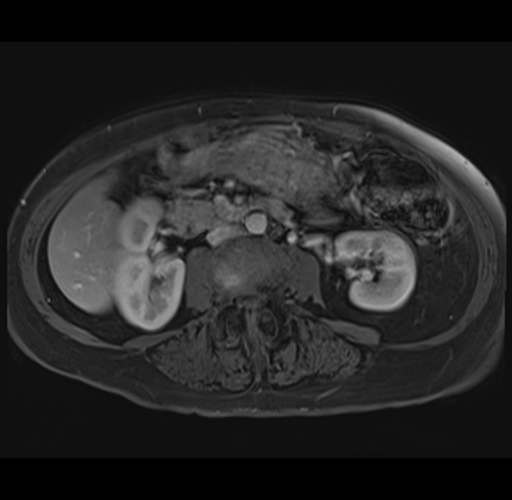

MRI T1